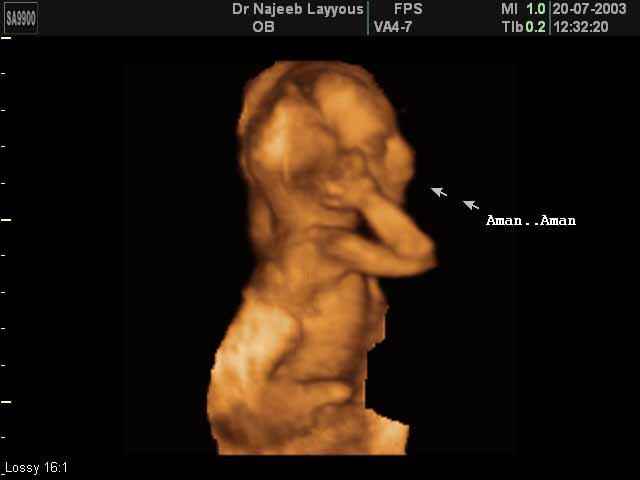

- 3D Fetal Profile Ultrasound Scan Photos

3D Second Trimester Ultrasound Scan Photos-second part of pregnancy | Dr N Layyous